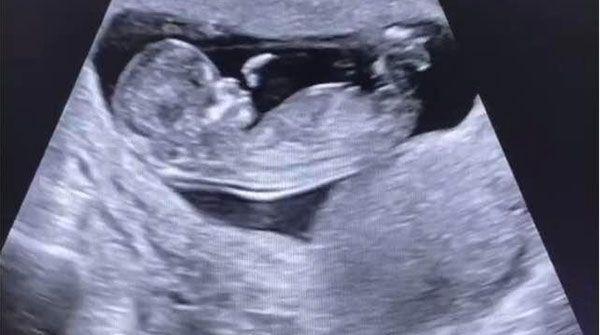

nt检查的结果会受到很多因素的影响,最直接的原因就是染色体发生了异常,染色体会导致nt结果偏离正常值范围,检测结果为2.3mm虽然是正常的,但是无法保证胎儿之后的发育不会有问题,所以无创DNA检查仍然要做。

目前医学界普遍都认定nt的正常值范围是2.5mm以下,只要处于此值的以下,都可以视为正常,也就是说从自然怀孕成功到孕13周的时间之内,胎儿并没有表现出明显的先天性疾病,这也是nt检查项目的主要意义。

2.3mm虽然属于正常,但是和正常的2.5mm相比来说,相差并不是很大,此时判断nt风险值为中低水平,这种情况是需要谨慎对待的,一方面要做好平时的防护工作,排除掉生活中可能导致胎儿可能出现染色体变异的因素,同时也要积极准备好下一次的检查。

2.3mm在nt检查中的确属于正常水准,但是这和后期选择是否做无创DNA并无直接关系,准确来讲,nt检查流程的进行和无创DNA过程并不冲突,而是两个阶段的检查,有所不同的是nt检查的最佳时间为孕13周,而无创DNA的检查时间约为20周左右。

nt检查实际上只是一种孕前期的粗略排查先天性遗传病的方法,很多关于疾病的细节是无法查出的,所以这也是有的孕妈nt值为2.1mm做无创检查的重要原因,但是需要指出的是,这种粗略的检查结果是具有很重要的参考意义的。nt检查通过,则大概率表示胎儿发育正常;若nt检查不通过,胎儿患病的风险就会成倍提升。